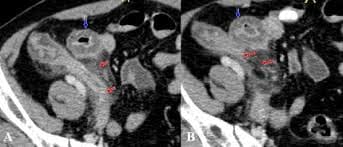

Ca 3: Bệnh nhân 69 tuổi, nam giới, đau hạ vị phải 2 ngày

Viêm ruột thừa cấp ở tiểu khung

Hình 3: A, ruột thừa nằm thấp ở tiểu khung, kích thước to thâm nhiễm mỡ xung quanh ruột thừa (mũi tên đỏ). B, lát cắt ngang gần đầu tận ruột thừa có dạng hình bia (target sign) (mũi tên đỏ).

Kết luận: viêm ruột thừa cấp ở tiểu khung